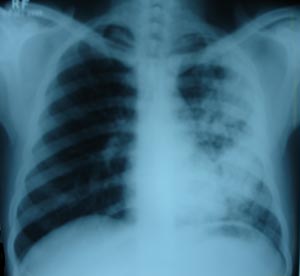

Left mid zone Koch’s infection 2

Right mid zone shows cluster of multiple fibronodular opacity, suggestive of unilateral koch’s infiltration. Patient on 4 drug AKT regimen.